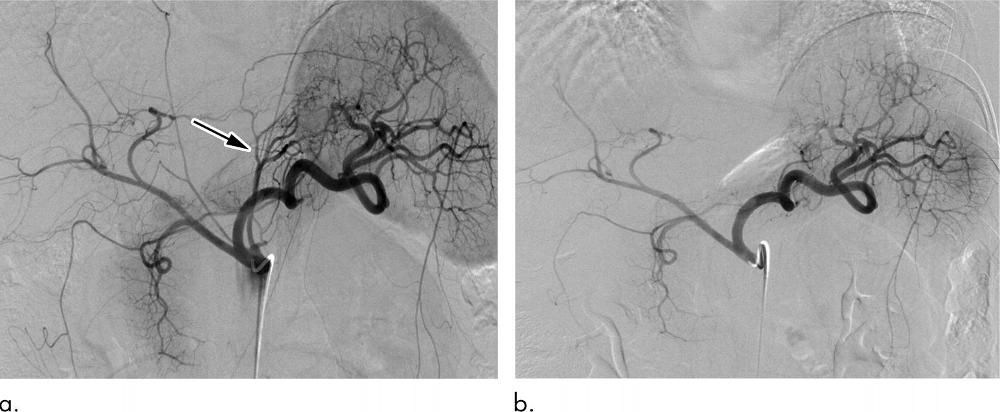

Figure 1. Figure 1: Bariatric embolization in a 41-year-old Caucasian woman with a baseline weight of 115 kg and a baseline body mass index (BMI) value of 48. At 12 months after embolization, she had weight loss of 16 kg (30 percent excess weight loss) and a BMI of 34. (a) Pre-embolization celiac angiogram showing classic left gastric artery (LGA) (arrow) anatomy, with the LGA arising from the proximal celiac artery and left gastroepiploic artery (GEA) branching from the gastroduodenal artery. (b) Postembolization angiogram showing successful embolization of the gastric fundus via the LGA and left GEA.